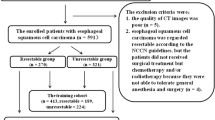

Of 210 participants recruited, 48 participants were excluded, generating a training set of 95 participants and a test set of 67 participants. The participant flowchart is provided in Fig. 1 showing the reasons for exclusions. Participant and dataset characteristics are shown in Table 1 and Supplementary Fig. 3.